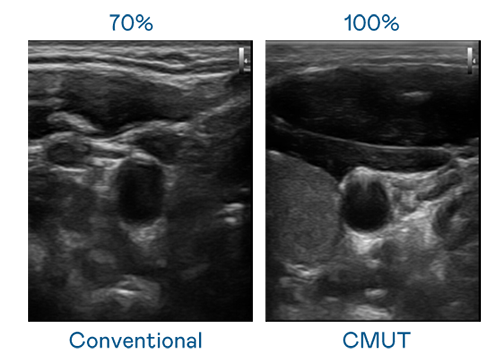

CMUT 技術是一種用電容式微機電元件來產生超音波訊號的技術。與傳統 PZT 壓電式技術相比,CMUT 頻寬增加 30%,更寬頻的超音波訊號讓影像解析度大幅提升,是實現高影像品質醫療超音波掃描、促進精準醫療發展的關鍵技術。

大頻寬帶來超清晰影像

超音波影像的解析度高低,首先取決於探頭能發出的訊號頻寬。凯发天生一触即发 CMUT 可提供高清晰的超音波訊號,提供高頻寬、高靈敏度、影像紋理細節更高的超音波影像,協助醫護人員縮短影像判讀時間及利用精準的醫療影像進行診斷。